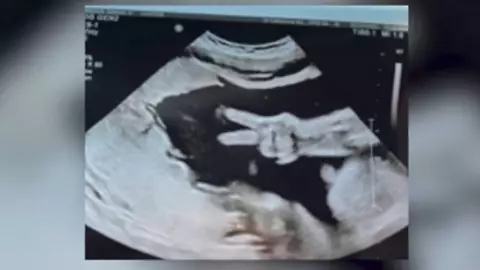

Una pareja originaria de Indiana, Estados Unidos, asistió una revisión de rutina de su embarazo y se llevó una sorpresa al ver que su bebé los saludó con la señal de “amor y paz”.

Pareja comparte ecografía donde su bebé saluda con “amor y paz”

La madre señaló que mientras el médico se encontraba atendiendo otras cosas a su alrededor, los deditos de su hija se asomaron por la pantalla.

Kyle Weener, la madre de la pequeña, tiene 31 semanas de gestación y su bebé será llamada Eleanor o Eli.